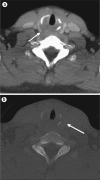

Actinomyces odontolyticus, a component of normal human flora, has been implicated in cervicofacial actinomycosis, which most commonly involves the perimandibular soft tissues and is characterized by slowly progressive abscess and sinus tract formation. Actinomycosis has rarely been reported to involve the larynx, and the imaging findings of laryngeal involvement have not been reported. We present a case of laryngeal actinomycosis with findings on computed tomography, magnetic resonance imaging, and positron emission tomography.